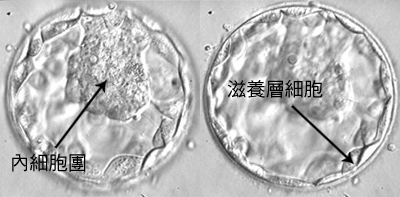

ÕøŖĶāÜń¦╗µżŹ’╝łBlastocyst Transfer’╝ē

ĶŠģÕŖ®ÕŁĄÕī¢’╝łAssistedHatching’╝ē